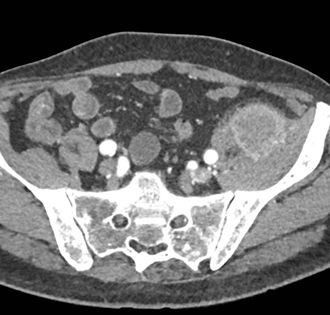

In this patient with left leg pain the best diagnosis is

abscess

hematoma

metastatic lesion to muscle

AV malformation